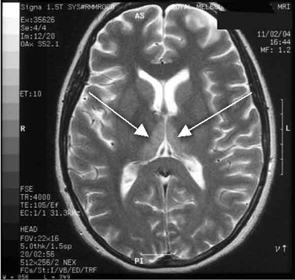

Haematological and biochemical test results were largely normal, but her serum levels of creatinine (0.04 mmol/L; normal range [NR], 0.05–0.10 mmol/L) and urea (2.2 mmol/L; NR, 2.5–6.1 mmol/L) were slightly low, and her INR (international normalised ratio) was 2.0 (NR, 0.8–1.2). There were also some elevated levels in her liver function test results: γ-glutamyl transferase, 60 U/L (NR, < 50 U/L); alanine aminotransferase, 486 U/L (NR, < 55 U/L); and bilirubin, 32 U/L (NR, 0–19 U/L). Cerebrospinal fluid (CSF) examination and magnetic resonance imaging (MRI) were also undertaken to exclude intracranial causes. The CSF findings were normal, but the MRI revealed bilateral thalamic lesions (Figure 2).

Given the new clinical features and her MRI result, a diagnosis of Wernicke’s encephalopathy was made. Thiamine deficiency was suspected to be secondary to hyperemesis gravidarum. Interestingly, her serum thiamine level was only marginally low at 64 nmol/L (normal range, 66–200 nmol/L). Therapy with pyridoxine, folic acid and intravenous thiamine replacement was commenced.

She made a rapid clinical recovery. Visual acuity returned to normal within 3 days and her ataxia, gaze limitation and neuropathy improved. Repeat MRI imaging 7 days later showed moderate resolution of the hyperintensities. Our patient went on to successfully deliver a healthy baby girl at 37 weeks’ gestation.

Our case is unusual in that visual deterioration was the first symptom of an evolving thiamine deficiency. There was a delayed presentation of the classical triad of Wernicke’s encephalopathy — ataxia, mental confusion and ocular gaze problems. Moreover, in our case, MRI scanning was able to detect sensitive neurological changes, raising the suspicion of thiamine deficiency. This information was important in prompt treatment of the condition when clinical signs began to emerge. Indeed there are reports of the usefulness of MRI imaging in diagnosing cases of Wernicke’s encephalopathy.7